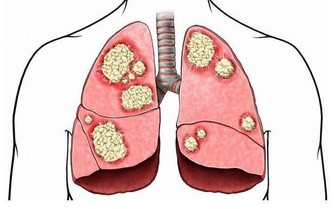

在各種不同類型的大腦變性中,儘管血管性癡呆和路易體癡呆也不罕見,但最常見的癡呆類型,還要數阿爾茨海默病,也就是我們常說的老年癡呆。

當然,由於癡呆影響記憶、思考和理性思維的能力,阿爾茲海默病常常會有以下常見症狀: